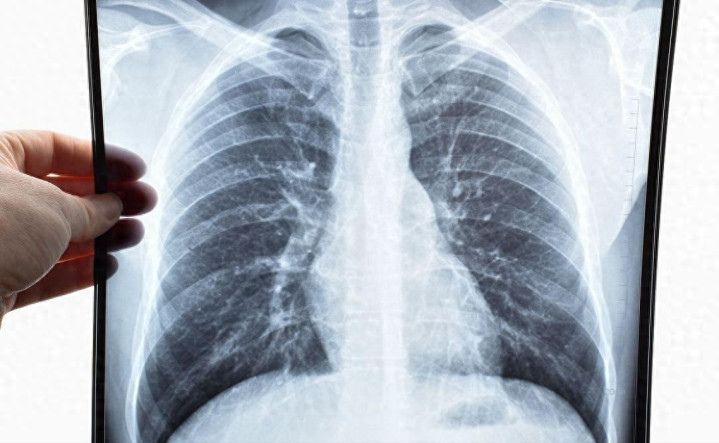

肺是个很娇气的器官,不抗折腾也不太能扛刺激。很多肺病,比如慢性阻塞性肺疾病、哮喘、肺纤维化等,发病时靠药物压着,但平时靠的就是生活调理。而吃,恰恰就是影响最大的部分。